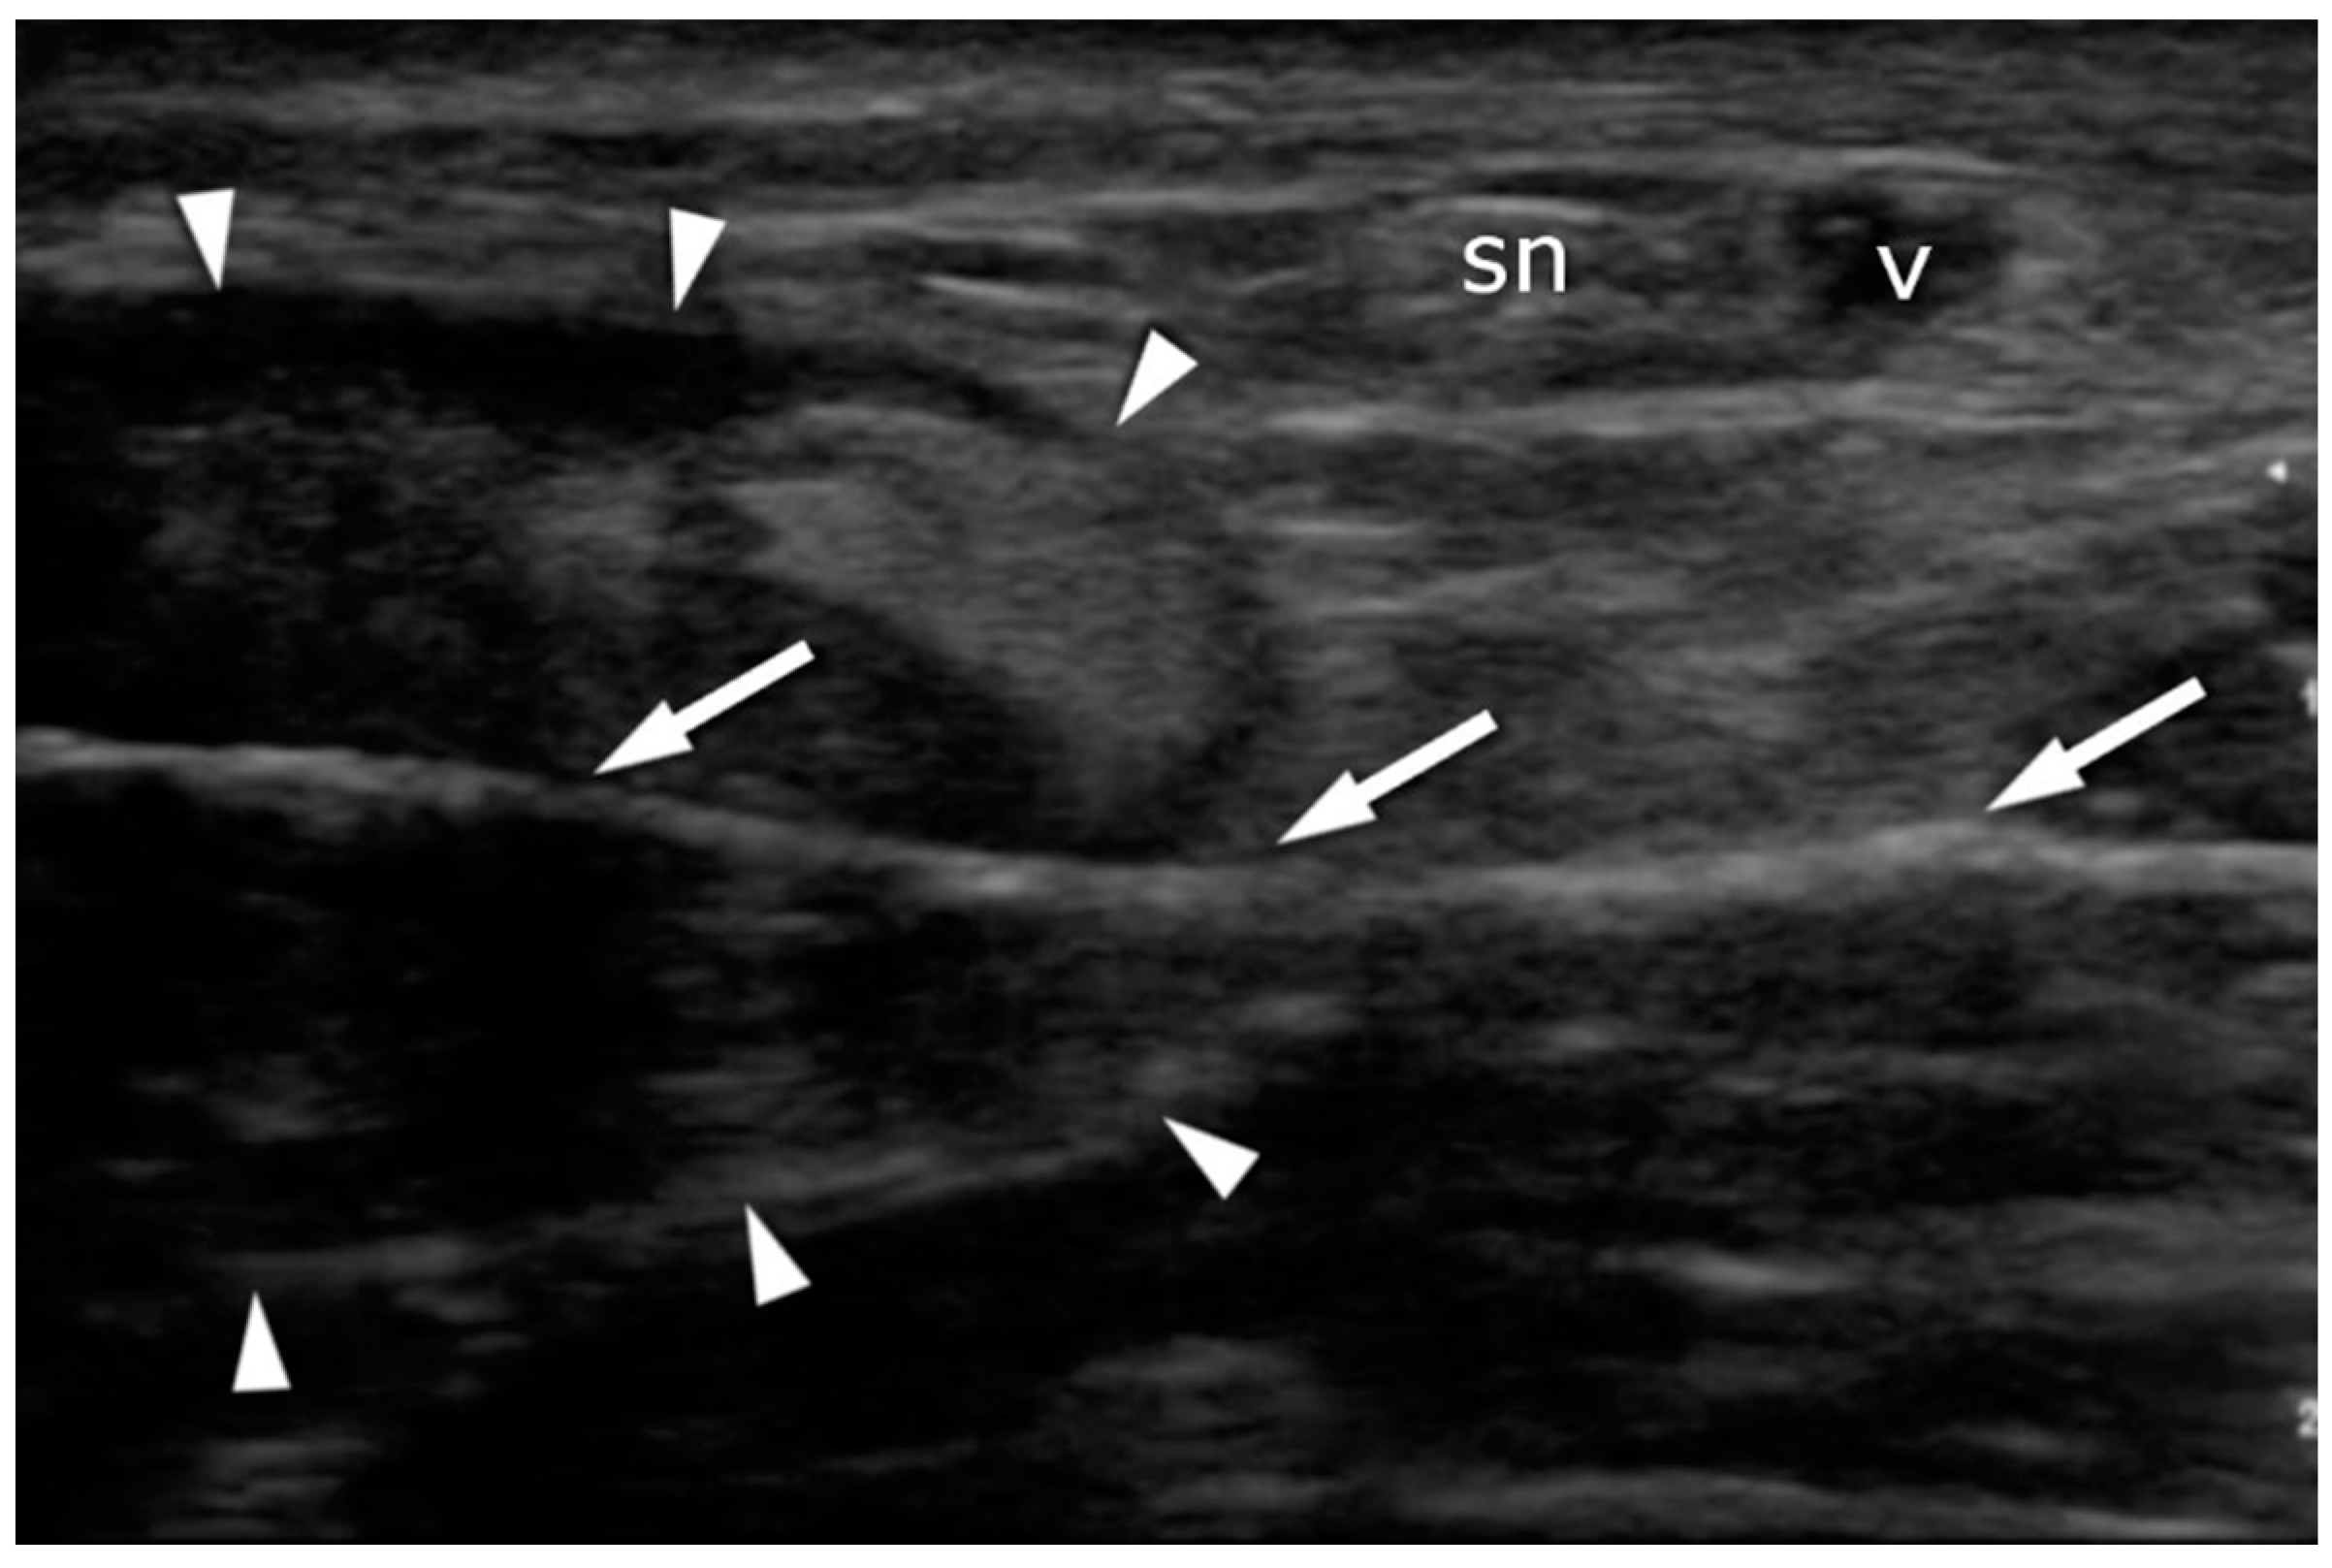

Figure 7.

Achilles tendon (arrowheads) after suture deployment: transverse plane. Note that the suture placement (arrows) avoids contact with the sural nerve (sn) and the vein (v).